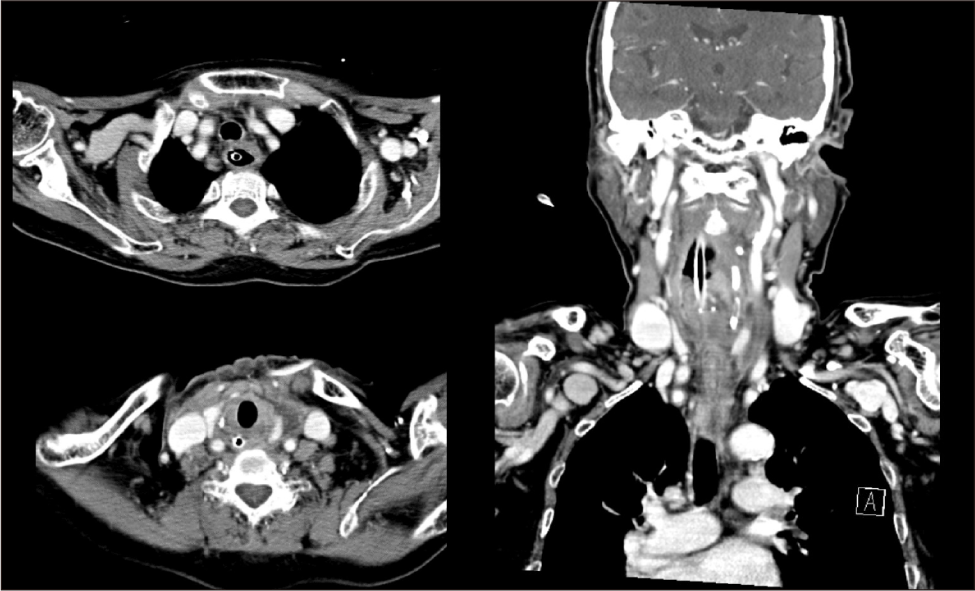

술 후 최고온도 39.3도의 발열 및 고감도C반응단백(high sensitive C-reactive protein) 8.37 mg/dL 상승 소견을 보였으며, 환자는 수술 후 위관 식이 과정에서 흡인(aspiration)이 발생하였다. 일부 흡인된 내용물이 음식물이 소화되지 않은 상태로 그대로 관찰되어, 이는 위 배출 지연보다는 괄약근 기능 부전(sphincter dysfunction)에 의한 것으로 판단하였다. 이에 따라 금식 후 흡인에 따른 폐 상태를 확인하기 위하여 경부 및 흉부 전산화단층촬영을 시행하였다. 영상 검사 결과 이전에 관찰되었던 하경부 및 식도 벽 내, 종격동의 액체 저류는 감소하였으나(Fig. 3), 양측 폐(특히 하부 의존 부위)에서는 반점형 경화, 간유리음영, 다발성 결절이 관찰되었고 간질음영의 두드러짐 및 경도의 분비물이 동반되어 기관지폐렴 및 무기폐가 의심되었다.

Fig. 3. Postoperative contrast enhanced CT scan demonstrating significant improvement of the previously noted intramural abscess within the esophageal wall. The previously observed low-attenuation area with peripheral rim enhancement has markedly decreased in size. Wall thickening is notably reduced, and surrounding inflammatory changes have subsided.

치료 전략은 병변의 범위와 환자의 전신 상태, 합병증 여부에 따라 달라진다. 국한된 병변의 경우 항생제 단독 치료로 호전된 보고가 있으나, 이 경우에도 엄격한 영상 추적 관찰이 필요하다. 최근에는 내시경 점막 절개 및 배농이 최소 침습적 치료로 부상하며 좋은 결과를 보이고 있다.4) 특히 단일 공동(single cavity) 형태의 병변에서 내시경적 배농은 효과적이고 합병증이 적은 치료법으로 보고된다. 그러나 내시경적으로 점막 변화가 명확하지 않은 경우에는, 시술 중 점막 천공 및 종격동염 악화의 위험이 증가하므로 내시경적 접근은 신중히 고려해야 한다.2,3) 병변이 다엽성(multiloculated)이거나 경부 및 종격동으로 파급되어 기도 압박이나 패혈증과 같은 위중한 상태로 이어진 경우에는 조기 개방적 수술이 필수적이다.5,6) 본 증례에서는 병변이 상부 식도와 심부 경부를 따라 종격동 상부까지 연장되어 있었으나, 영상에서 종격동 내에 명확한 국소 농양강이 형성되어 있지는 않았고, 고령 환자에서 경부 접근만으로도 충분한 배농이 가능하다고 판단하여 개방적 경부 배액술을 우선 선택하였다.